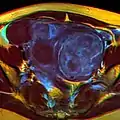

MRI image with multiple uterine leiomiyomas